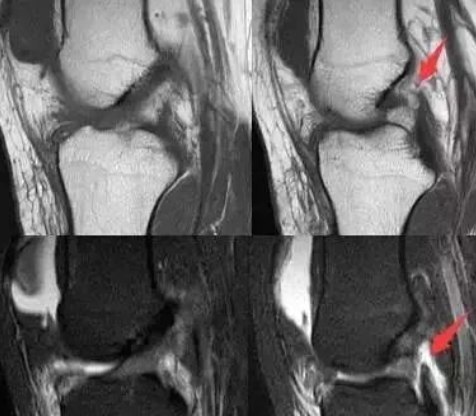

后交叉韧带损伤的分级!